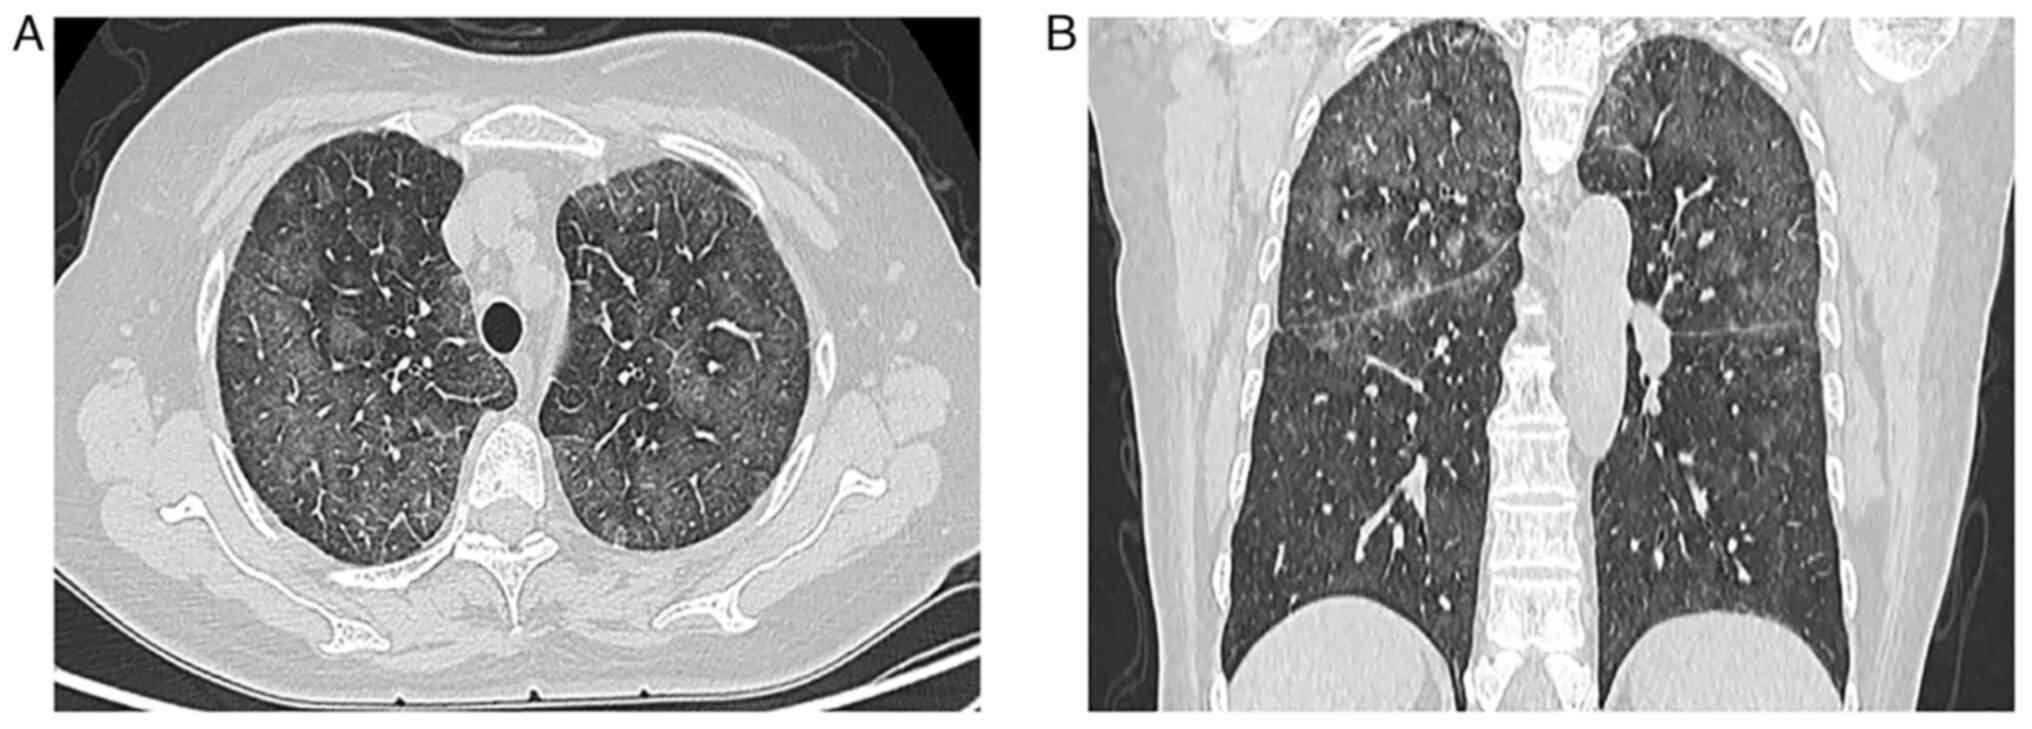

A 69-year-old female patient was referred to Nanjing Drum Tower Hospital in March 2010 with a 2-month history of coughing with white sputum without cause and progressive dyspnea on exertion. In addition, the patient experienced fever (37.3-39.8°C) for a duration of 1 week. A physical examination revealed cyanosis of the lips, edema of the lower limbs, clear consciousness, no skin rashes, nodules or hemorrhagic spots and no hepatosplenomegaly. After admission, CT examination was performed. The CT images demonstrated increased attenuation in bilateral lung parenchyma with multiple ground-glass opacities (GGOs) and part progression to consolidation (Fig. 1A), especially on the superior lobes. Interlobular septal thickening and partial thickening of bronchovascular bundles as well as ‘tram track-like’ changes were observed (Fig. 1A), along with no lymph node enlargement within the mediastinum or hilus (Fig. 1B). During hospitalization, treatment for infection using imipenem/cilastatin sodium (0.5 g/8 h) with intermittent use of acetaminophen tablets (0.5 g) for fever reduction was administered, but no notable effect was revealed. Finally, pulmonary IVLBCL was diagnosed using transbronchial lung biopsy (TBLB). Abnormal lymphoid cells distributed within the blood vessels were observed under a light microscope, and the diagnosis of pulmonary IVLBCL was further confirmed through immunohistochemical staining. The patient rejected chemotherapy treatment and died due to respiratory failure shortly (20 days) after diagnosis.

Figure 1.

Case 1. Axial computed tomography slices of the chest images showed (A) increased attenuation in bilateral lung parenchyma, characterized by areas of ground-glass opacities and consolidation, and interlobular septal thickening partial (arrows) as well as ‘tram track’ appearance (arrowhead), and (B) no lymph node enlargement within mediastinum or hilus.

Compared with other pulmonary lymphoma, IVLBCL generally does not involve lymphadenopathy or a localizing solid mass, as the lymphomatous cells mainly involve the pulmonary arteries and capillary beds (14). Results of CT assessments are diverse and can be inconspicuous or show GGO and interstitial infiltration (11,12,14). In the cases of the present study, patchy areas of GGO existed on patient presentation and this accentuated the bilateral lung attenuation resulting from pulmonary vascular obstruction. In case 1, the chest HRCT revealed bilateral disease that was pneumonia-like, which progressed partly to consolidation. Due to local interlobular septal thickening along with the thickening of bronchovascular bundles, new GGO indicated lymphatic and hematological spread. The other 3 cases showed bilateral GGOs, micronodules and thickened interlobular septa in the lungs without pleural involvement, which suggested that the disease may spread along lymphatic structures. In case 2, the pulmonary shadows completely disappeared after a short-term chemotherapy schedule, which supported the diagnosis of IVLBCL. The etiology of GGO (heterogeneous and partially consolidated) in all four patients remains unclear. Malignant cells may invade the alveolar space, resulting in consolidation (increased density) on CT imaging. Increased diffuse density in bilateral lungs with GGOs and thickening of interstitial septum needs to be distinguished from non-neoplastic lesions, such as interstitial diseases and mechanical pneumonia, which may also present as progressive dyspnea with cough and other manifestations of obstructive ventilation. TBLB and bronchoalveolar lavage fluid can be used to aid diagnosis. Undoubtably, IVLBCL needs to be differentiated from venous thromboembolism and other intravascular malignancies of the lung, including lymphomatoid granulomatosis, angiocentric lymphoma and pulmonary involvement by acute and chronic lymphocytic leukemias (3). At this point of the patient examination, the clinical manifestations and CT characteristics may be non-specific, and immunohistochemistry will provide great help for the correct diagnosis.